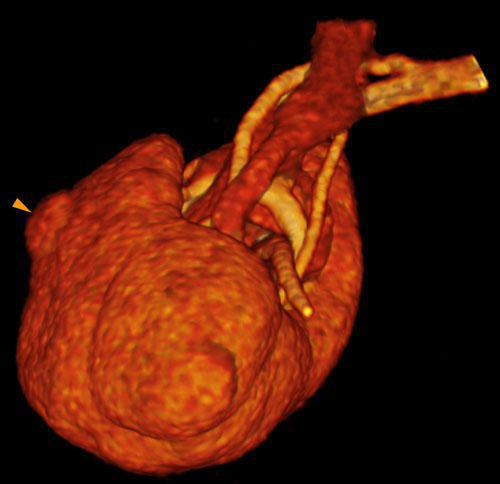

Hipernefroma 1